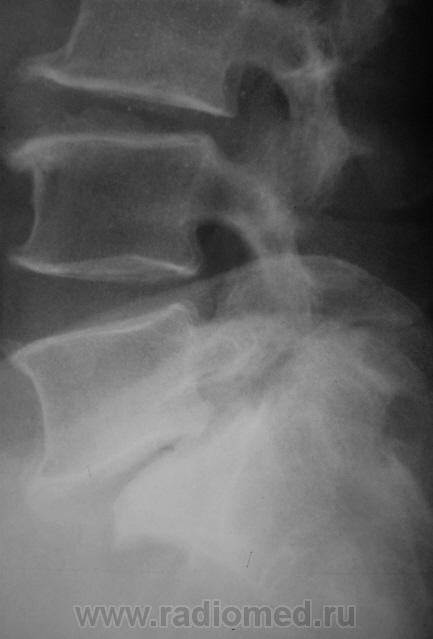

Спондилолистез L5-S1 - истинный, поэтому природа сама набедокуривши, сама и оберегает. Трудно представить безсимптомное течение, если бы это было последствием травмы. Очень рад, что Андрей Юрьевич приводит выдержки из Рейнберга. Судя по желтизне страниц - это первое издание.

По данному случаю:на мой взгляд, он является примером того, что попытки обяснить клинику(страдания пациента) только изменениями на R-граммах несостоятельны (если бы, у пациентки были жалобы,скажем на боли в области поясницы, сделали бы вывод-"что вы хотите?!-деформирующий спондилёз, да ещё спондилолистез- из-за этого и болит"). Думаю, многие сталкивались такими направлениями: "Направляеться на R-графию пояснично-крестцового отдела позвоночника.D.S.:Исключить остеохондроз ".

А во сколько лет человек заимел все -озы? И спондилолиз с листезом 2 ст?